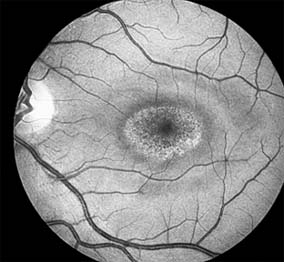

MACULAR EDEMA

Retinal edema involving the macula may be associated with a variety of intraocular inflammatory diseases, retinal vascular diseases, intraocular surgery, inherited or acquired retinal degenerations, medications, macular membranes, or unknown causes. Macular edema may be diffuse, with nonlocalized intraretinal fluid causing thickening of the macula. When edema fluid accumulates in honeycomb-like spaces of the outer plexiform and inner nuclear layers, it is called cystoid macular edema. On fluorescein angiography, fluorescein dye leaks from the perifoveal retinal capillaries and accumulates in a flower-petal pattern about the fovea (Figure 10-4).

Figure 10-4

Figure 10-4: Flower-petal pattern of fluorescein dye in a patient with cystoid macular edema after cataract surgery.